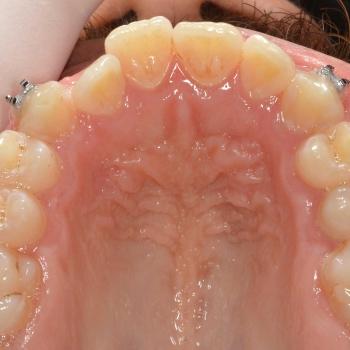

János egy másik fogorvos által befejezett, illetve később részlegesen újrakezdett fogszabályozó kezelés sikertelensége miatt keresett fel rendelőmben. Az első konzultáció alkalmával több esztétikai és funkcionális hibát is észrevettünk, többek között keresztharapást, enyhe nyitott harapást, torlódást, egyoldali Class II harapási eltérést, az alsó és felső őrlőfogak egymással nem harmonizáló dőlését, illetve az alsó középvonal funkció közbeni eltolódását balra.

A kezeléshez János hagyományos fém fogszabályozót választott, melyet kiegészítettünk a legkülönfélébb intermaxilláris gumihúzásokkal, illetve egy speciális belső oldali fogszabályozó ívvel, ami segített az alsó őrlőfogakat a nyelv irányába dönteni.